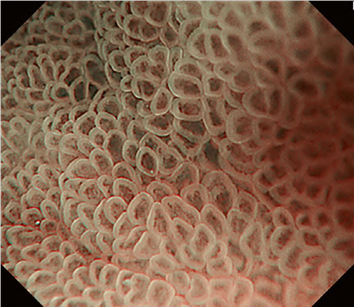

The working group members carried out a systematic review of the English literature to determine widely accepted diagnostic systems. Consequently, the best-accepted diagnostic system was proven to be the VS classification system. Based on this system, MESDA-G was constructed using an evidence-based approach (. Figs. 3, 4, 5, and 6) [2]. First, lesions suspicious for EGC should be detected by careful inspection using conventional white-light endoscopy. Subsequently, magnified observations should be performed. Owing to the high sensitivity of the demarcation line [8], if it is absent, the suspicious lesion is diagnosed as noncancerous (. Fig. 4a, b). However, if the demarcation line is present, further assessment is required to determine the presence of an irregular MV or MS pattern. If an irregular MV and/or MS pattern is detected, the suspicious lesion is diagnosed as cancerous (. Fig. 6a, b) [1, 5, 6, 8]. If both the irregular MV and MS patterns are absent, the tumor is diagnosed as noncancerous (. Fig. 5a, b) [1, 5, 6, 8].